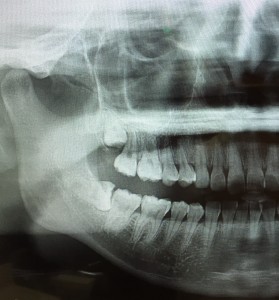

親知らずは横向きに生えていると、手前の歯にぶつかって、それ以上出てきません。

半分ぐらい歯茎の外に出ている場合は、どうしても手前の歯との間に汚れがたまり、そこから手前の歯を含めて虫歯になったり、歯周病が進んだりします👿

親知らずの手前の歯は、一生必要ですので、症状を繰り返しながら段々と悪くなるのを待つよりは、原因となる親知らずを抜歯する事が望ましいです。